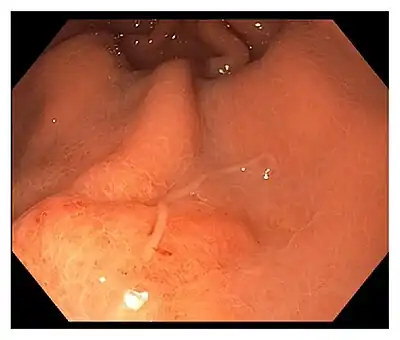

A typical endoscopy of the acute gastric form shows a worm embedded within the submucosa, with a visible lesion at the site of entry, and a thicker oedematous stomach lining.[3] In patients with chronic gastric infection, there is often an ulcer or inflamed mass visible on the stomach lining.[3]

Treatment

The worm is often removed during the gastrointestinal endoscopy, which alleviates the symptoms within hours.[3][7] However, surgical removal of the affected tissue must be conducted when the worms are already buried deep in the viscera.[3][7]